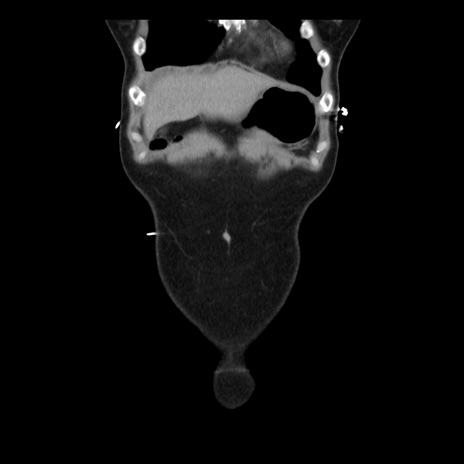

横断像